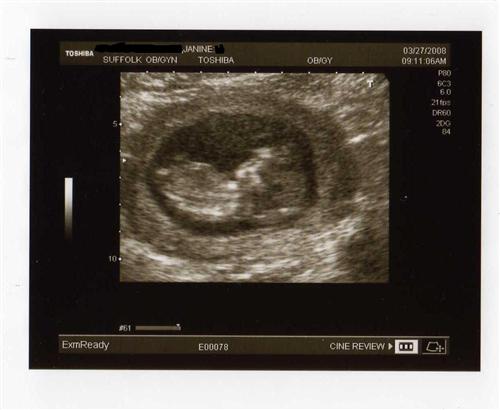

I wanted to share my 12 week sono pics that I had yesterday. Our little one was quite active, as I had a sugery cereal in the morning. Baby was rolling and waving, showing us all five fingers and was rubbing his/her eyes like it just woke up. They said baby looks good and healthy so far.

Showing the hiney-rubbing his/her eyes with its right hand.